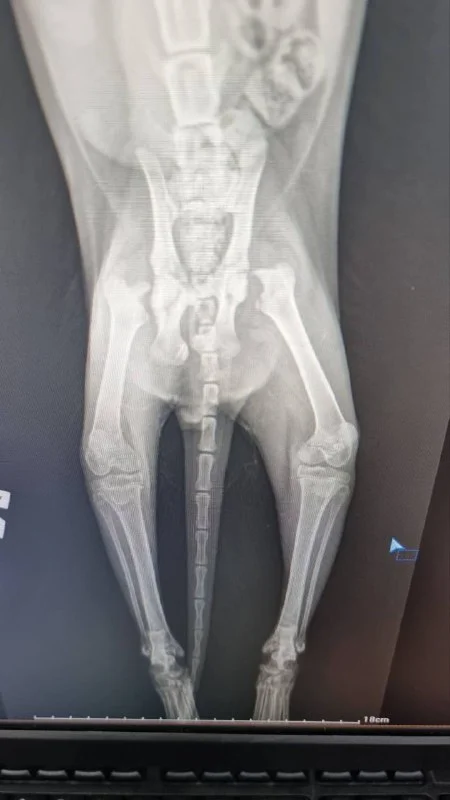

Группа, добрый вечер!

Любая незначительная сумма для вас. 130 евро занесла в клинику уже. Прилагаю чек. Благодарю заранее! Всегда готова в личку ответить на все вопросы по котику, и предоставлять апдэйты.